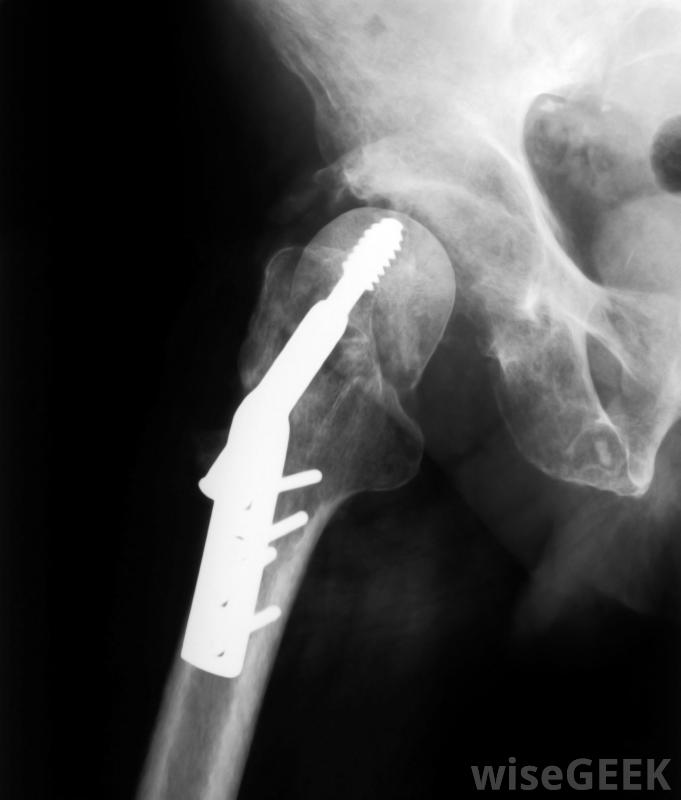

什么是動態髖螺釘(Dynamic Hip Screw)?

動力髖螺釘是一種用來固定髖部骨折的裝置。髖關節的一半由一塊圓形的骨頭組成,稱為股骨頭,由股骨頂部的一個狹窄的股骨頸或大腿骨支撐。這個圓頭位于髖骨中的一個叫做髖臼的中空處,在那里它能平穩地旋轉,導致髖關節的正常運動。有時,諸如跌倒之類的損傷會折斷股骨頸,然后需要在骨頭愈合時使用動力髖螺釘之類的裝置固定股骨頭。使用動力髖螺釘的優點在于,它可以讓患者在術后很快走動,避免長時間臥床休息以及胸部感染和腿部血栓的相關風險。在DHS手術期間,外科醫生在骨折處放置一個大的金屬螺釘,用鋼板和一些小螺釘將骨頭固定在一起。固定髖部骨折的手術是一種矯形外科手術。矯形外科手術包括治療涉及骨骼及其附屬肌肉的問題。當使用髖部螺釘等矯形植入物時,這種技術有時被稱為滑動螺釘固定src="/img/0801/radiography-scan-of-hip-area.jpg"/>從臺階上摔下來可能導致老年人髖部骨折動力髖關節螺釘手術可能需要住院幾天。手術通常是在全身麻醉下進行的,因此患者在手術過程中處于睡眠狀態,在手術前的幾個小時內不能進食或喝水。偶爾,可能會使用麻醉藥物使腰部以下的身體麻木動態髖關節螺釘用于固定髖部骨折。手術期間,動力髖螺釘被插入股骨。它由一個大螺釘組成,它以一定的角度固定在股骨頭上,與金屬板相連,金屬板沿著股骨軸垂直定位,用較小的螺釘固定到位。外科醫生使用X射線圖像確保髖螺釘的準確定位X光圖像有助于確保動力髖螺釘的準確定位。手術后,通常在同一天晚些時候可以正常進食和飲水。一滴點滴會連接到手臂的靜脈,這通常會被移除,盡管引流傷口的管子可能會在原地停留一段時間。止痛藥可以緩解任何不適動態髖關節螺釘固定術可能需要住院幾天。在臥床休息一天后,鼓勵患者使用步行架行走。動態髖關節螺釘設計意味著骨折的髖部在愈合時有可能承受重量。保持活動有助于降低腿部發生血塊的風險,并減少躺在床上引起壓瘡的幾率。移動也可以有助于刺激呼吸,降低發生胸部感染的可能性。一旦患者能夠獨立、安全地行走,他們通常可以回家。動態髖關節螺釘使患者能夠為了避免長時間臥床休息,允許患者在術后不久走動。物理治療師可以幫助患者從手術中恢復過來,修復髖部骨折髖關節手術后一天,鼓勵患者使用步行架四處走動。